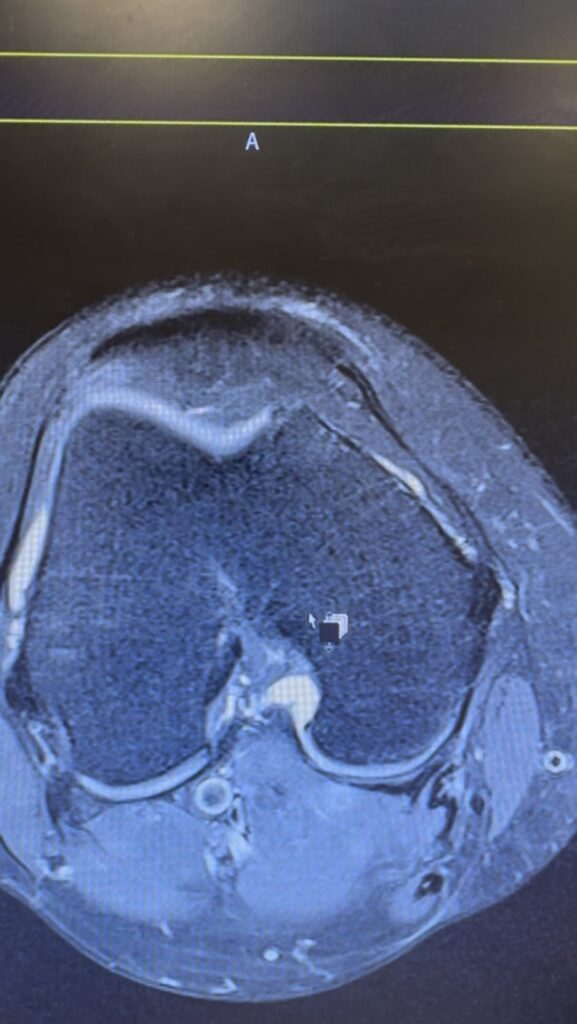

I should have posted this at the beginning of the month. I finished this early this month, but at first, I wasn’t able to upload because my MacBook was sent for repair, and then I kept forgetting once I got it back. Time really flies, and it’s now already the end of the month, and even the 1st February if you consider Hong Kong’s time, which is my birthday. Hope I get wiser as my age goes up, and good luck with whatever I’m doing. (Very important: speedy recovery of my poor knee!)

The past year, 2025, was a lot for me: injured my knee, graduated from uni, started to build a place where I call home, and got my first job. It was a year in which I finally gained something I’d put effort into, but it was also a year in which everything challenged me. I had lots of wonderful moments in the year, but there were more dreadful moments, which made me question why I would even start doing the things I have been doing. I just hope that in the forthcoming 2026, most things will be back on track. It’s my another year in this country, where I now call home, with a new journey ahead of me.